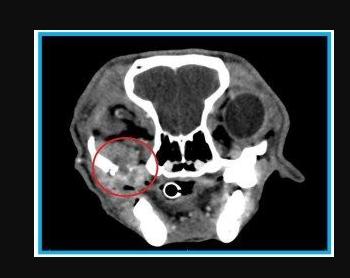

CT图像显示了许多黑色素瘤表现出的浸润性生长模式

通常在手术前进行头部或颈部的CT扫描以确定疾病的严重程度。但如果肿瘤入侵到骨骼组织,则难以去除。